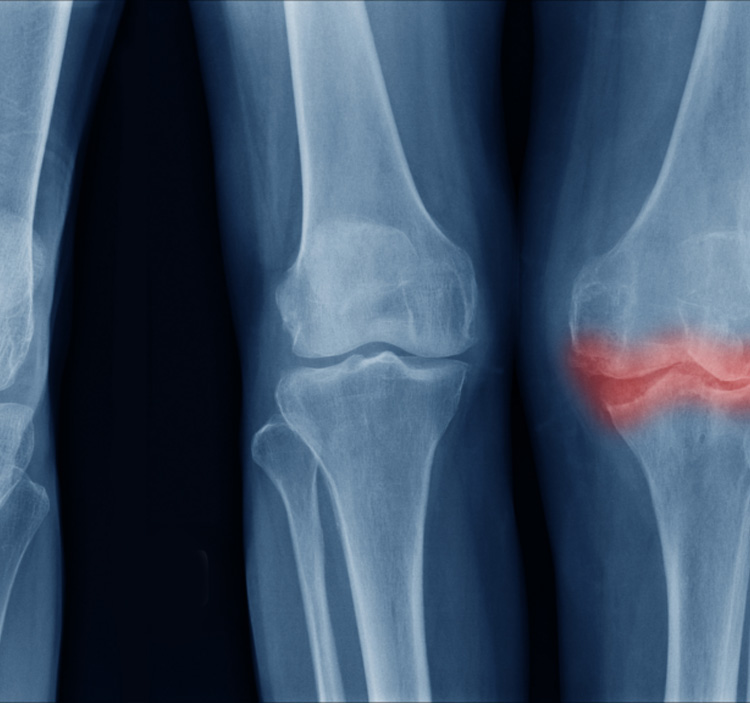

Osteoarthritis (OA) is a progressive joint disorder resulting in joint pain, stiffness, and reduced mobility due to cartilage and synovial fluid degradation. Viscosupplementation—injecting hyaluronic acid-based solutions—is a validated approach to restore lubrication, shock absorption, and joint function.

Osteoarthritis is a complex, multifactorial degenerative joint disease that affects the entire joint structure—including articular cartilage, subchondral bone, synovial fluid, and periarticular tissues. While it can affect any joint, it is most commonly found in the knees, hips, hands, and spine.

3. Subchondral Bone Remodeling and Sclerosis

The bone beneath the cartilage (subchondral bone) thickens and undergoes abnormal remodeling in OA.

• Loss of cartilage exposes bone to excessive stress.

• Osteoblast activity increases, forming sclerotic (hardened) bone and osteophytes (bone spurs).

• This disrupts normal joint architecture and increases pain.